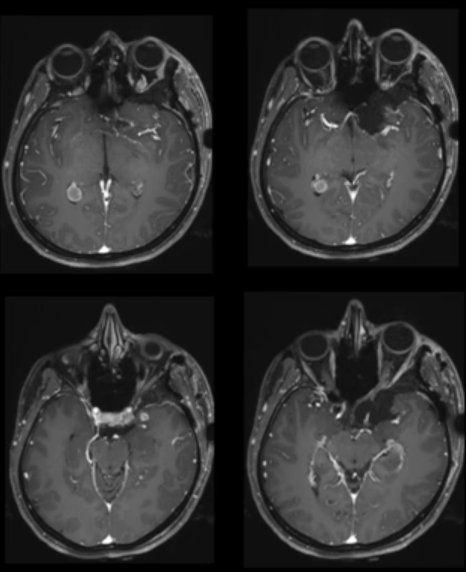

▼术后MRI显示肿瘤全切除